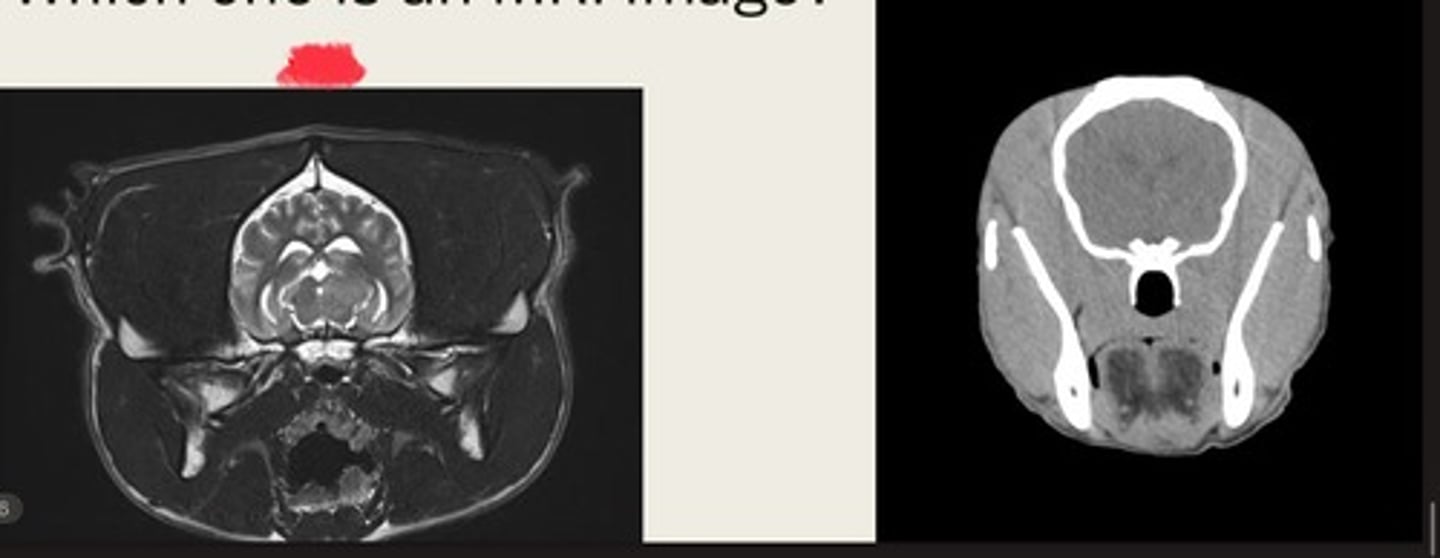

-cross sectional

-same area

-TRANSVERSE PLANE

how are these images the same?

right- bright bone

left- less bright bone, more definition in tissue

how are these images different?

left- MRI

right- CT

which one is the CT and which is the MRI?